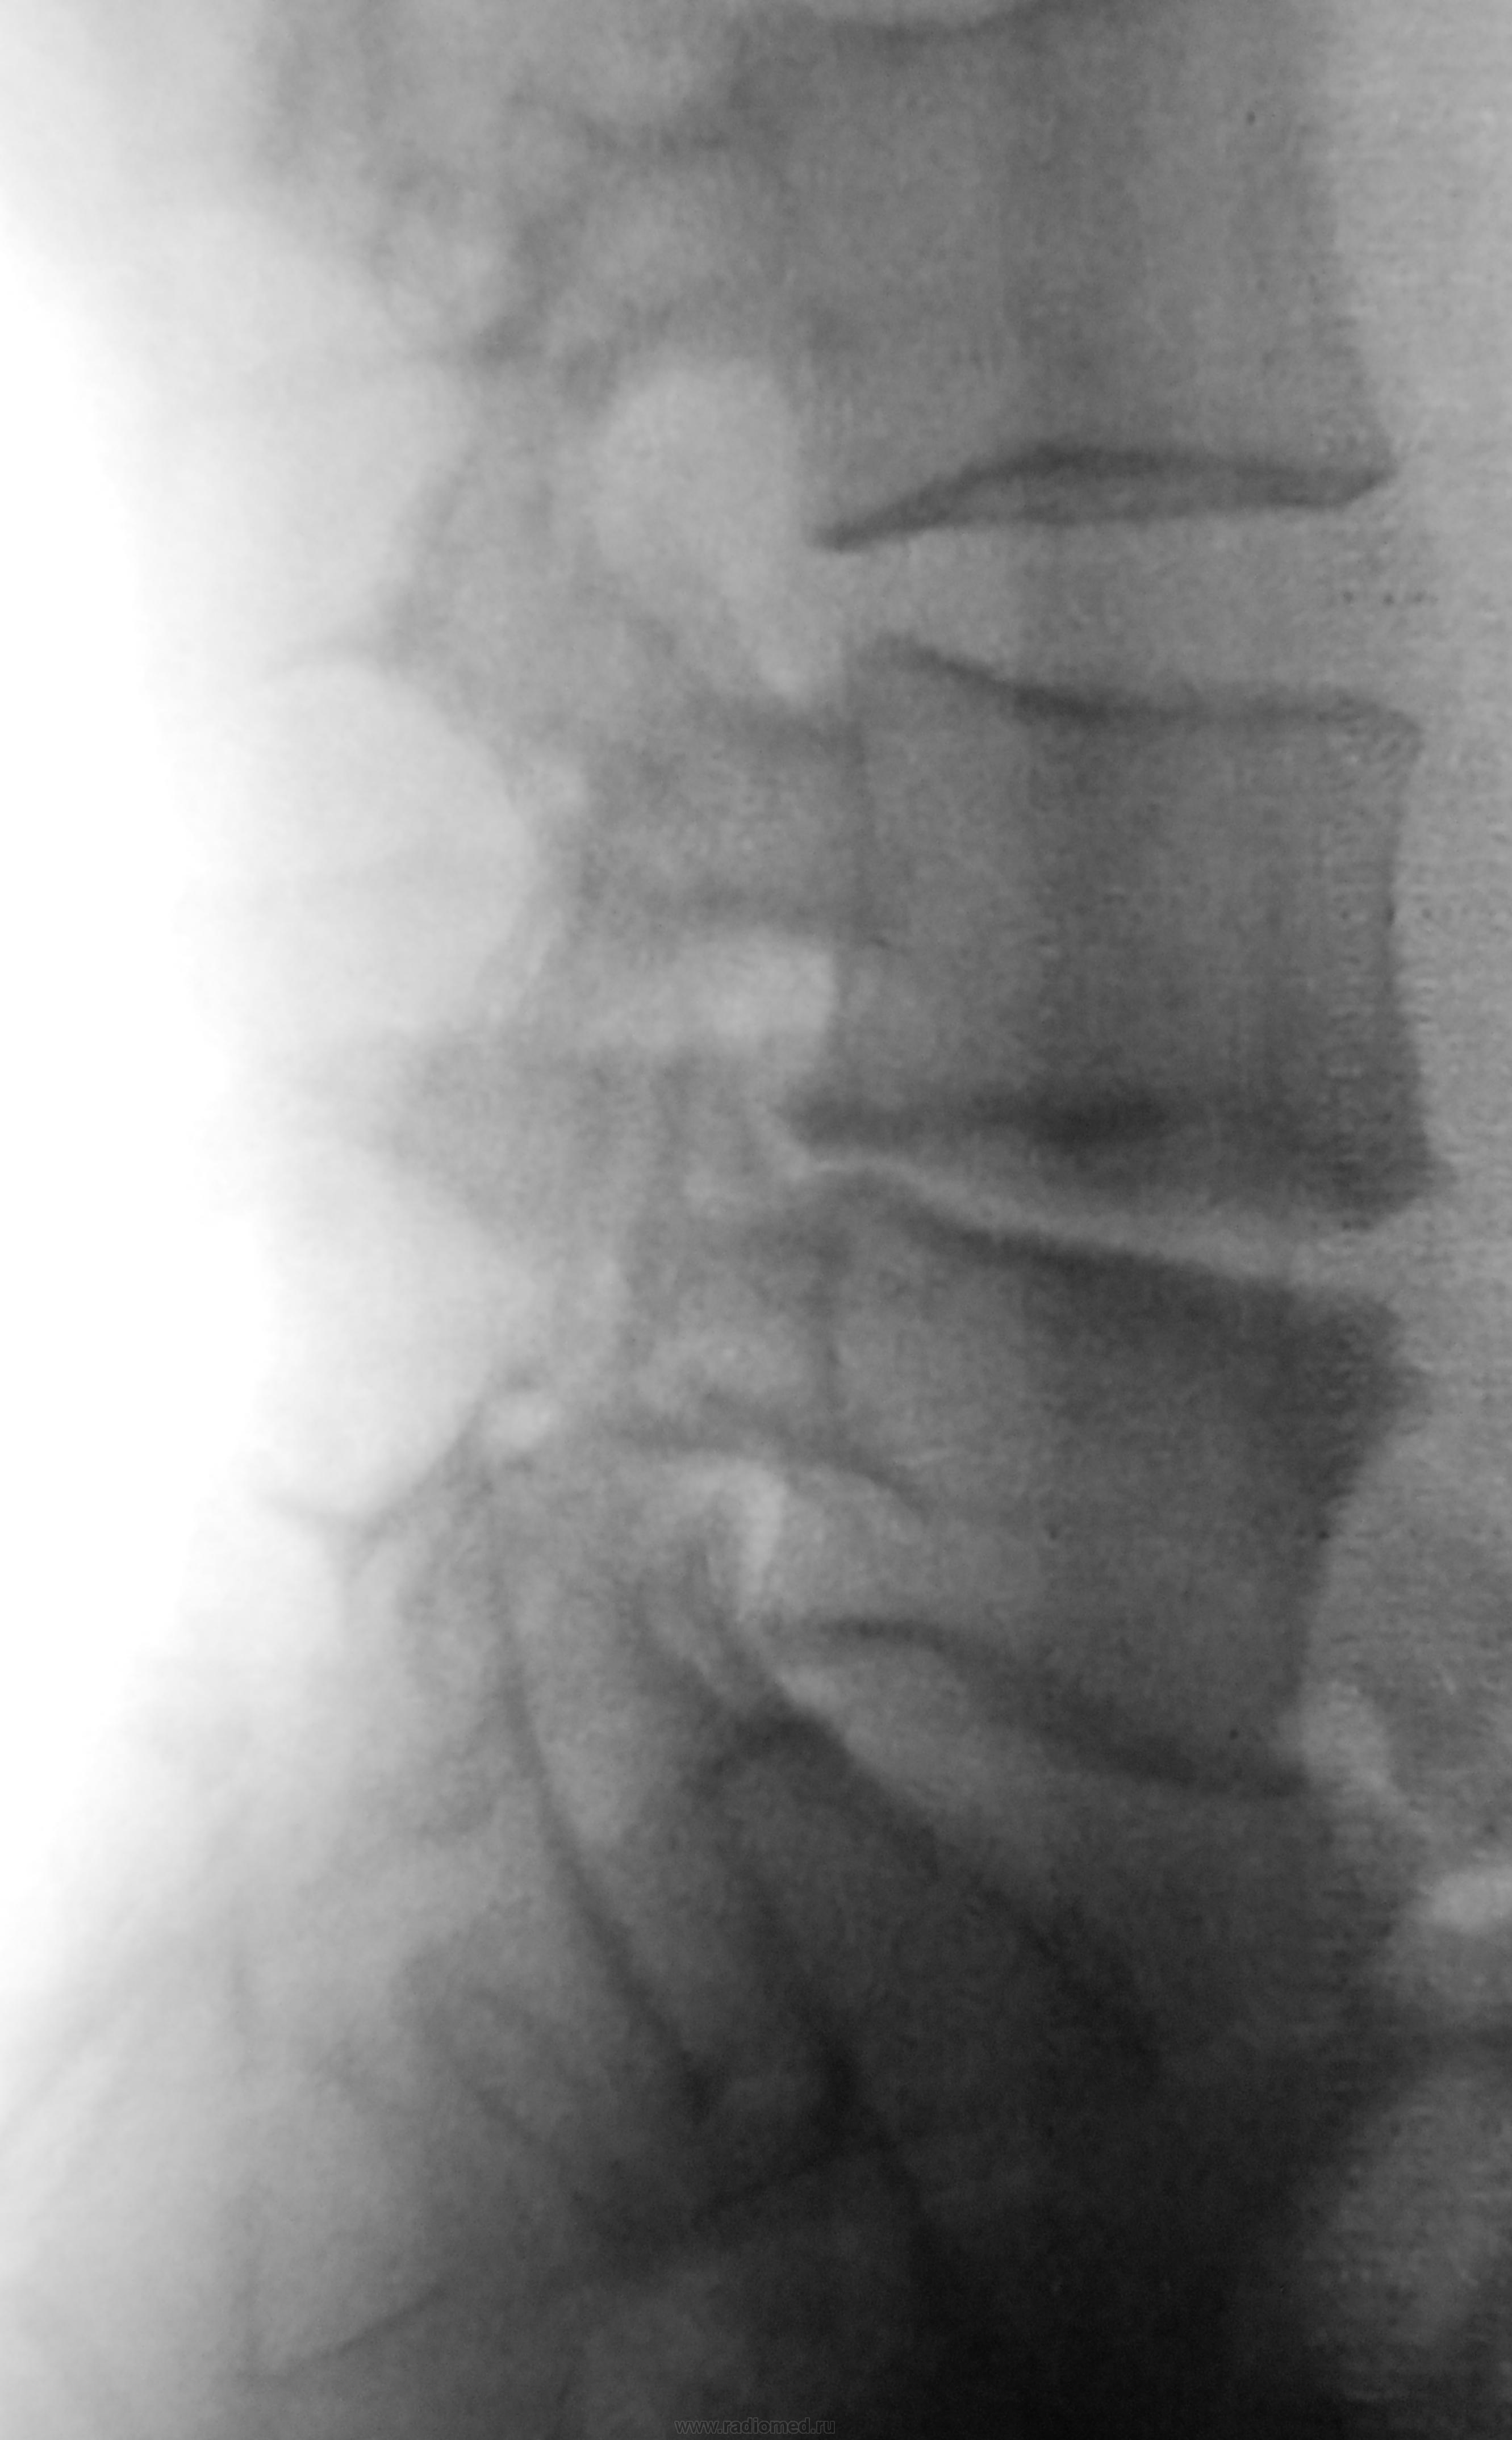

При всем к Вам уважении, возражу... И существенно. Нельзя путать грыжи Шморля и Поммера (грыжевые пролабации диска через ЗАМЫКАТЕЛЬНЫЕ ПЛАСТИНЫ в тела позвонков, выглядят от легкой волнистости до вполне оформленных четко очерченных склерозом грыжевых узур) с задними грыжами м/п диска, читай - задней протрузией через трещины фиброзного кольца диска в сторону спинального канала или м/п отверстий. Грыжи Шморля - бессимптомные, грыжи диска - клинически сами знаете, что дают - копрессию корешков и сдавление спинного мозга. К тому же, если бы так легко все рентгенологи могли рисовать и ставить в заключении задние грыжи дисков, как это сделали Вы, половина КТ и МрТ исследований поясничного отдела исчезли бы из медицины.

Грыжи Шморля.

Грыжи Шморля находятся внутри тела позвонка. Как показал Валентин Львович. То, на что вы указывали могло бы быть межпозвоночной грыжей)

Да, по поводу грыж (пузырьков) Поммера не часто можно услышать.